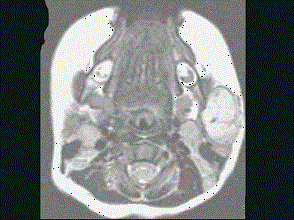

问题 40岁,患者,左面部渐进性增大的包块,MRI检查如图所示,应考虑为 ( )

选项 A、左面部脂肪瘤 B、左面部神经纤维瘤 C、左面部囊肿 D、左面部脓肿 E、左面部毛细血管瘤

答案 E